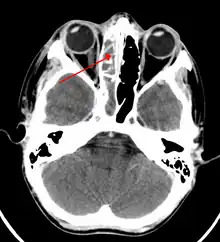

The proximity of the brain to the sinuses makes the most dangerous complication of sinusitis, particularly involving the frontal and sphenoid sinuses, infection of the brain by the invasion of anaerobic bacteria through the bones or blood vessels. Abscesses, meningitis, and other life-threatening conditions may result. In extreme cases, the patient may experience mild personality changes, headache, altered consciousness, visual problems, seizures, coma, and possibly death.[16]

Sinus infection can spread through anastomosing veins or by direct extension to close structures. Orbital complications were categorized by Chandler et al. into five stages according to their severity (see table).[26] Contiguous spread to the orbit may result in periorbital cellulitis, subperiosteal abscess, orbital cellulitis, and abscess. Orbital cellulitis can complicate acute ethmoiditis if anterior and posterior ethmoidal veins thrombophlebitis enables the spread of the infection to the lateral or orbital side of the ethmoid labyrinth. Sinusitis may extend to the central nervous system, where it may cause cavernous sinus thrombosis, retrograde meningitis, and epidural, subdural, and brain abscesses.[27] Orbital symptoms frequently precede intracranial spread of the infection . Other complications include sinobronchitis, maxillary osteomyelitis, and frontal bone osteomyelitis.[28][29][30][31] Osteomyelitis of the frontal bone often originates from a spreading thrombophlebitis. A periostitis of the frontal sinus causes an osteitis and a periostitis of the outer membrane, which produces a tender, puffy swelling of the forehead.

If an odontogenic infection or a complication of a dentistry procedure involves the maxillary sinus, odontogenic sinusitis (ODS) may ensue.[34] Odontogenic sinusitis can often spread to other sinuses such as the ethmoid, frontal and (less frequently) sphenoid sinus, and even to the contralateral nasal cavity.[35] In rare instances, these infections may involve the orbit, causing orbital cellulitis, which may in turn result in blindness, or determine central nervous system complications such as meningitis, subdural empyema, brain abscess and life-threatening cavernous sinus thrombosis.[36][37]

Infection of the eye socket is a rare complication of ethmoid sinusitis, which may result in the loss of sight and is accompanied by fever and severe illness. Another possible complication is the infection of the bones (osteomyelitis) of the forehead and other facial bones – Pott's puffy tumor.[16]